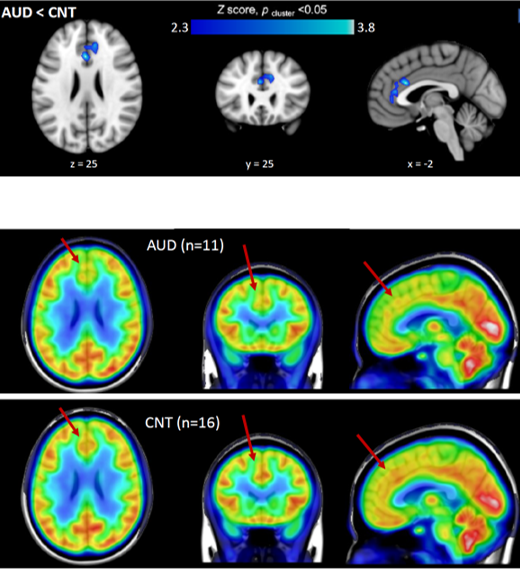

Alcohol use disorder (AUD) is a devastating illness with a profound health impact. In the past decade, research on epigenetics has revealed that AUD may have a strong connection with dysfunction of chromatin-modifying enzymes, and among them, histone deacetylases (HDACs) are frequently implicated. HDACs hold a great potential as therapeutic targets and the investigation on HDAC expression changes in the development of AUD will directly advance understanding of the importance of epigenetic roles in the neurobiology of AUD. We are currently using the PET imaging probe [11C]Martinostat to explore this.

In our pilot study, we use a machine learning approach to identify and validate non-invasively in vivo human brain histone deacetylase (HDAC) PET neuroimaging biomarkers using [11C]Martinostat radiotracer for differentiating case-control cases in the context of precision medicine.